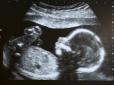

Вага батьків пов’язана із здатністю зачати дитину - несподівані дані дослідження

Вага батьків може суттєво вплинути на їхню здатність зачаття дитини. Такого висновку дійшли вчені з Нідерландів, передають Патріоти України. Дослідники встановили, що надмірна або недостатня вага пов’язана із зниженою фертильністю. На кожну одиницю збі...